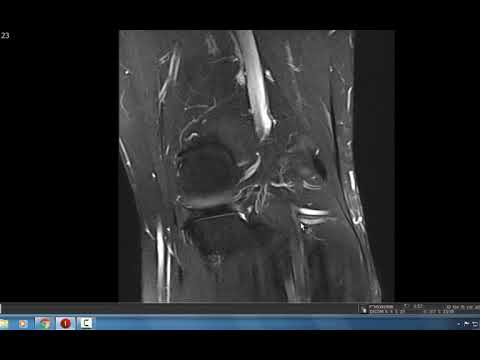

Систематическая интерпретация МРТ коленного сустава: дополнительные случаи

Дополнительные случаи, рассмотренные доктором Болье, руководителем отделения опорно-двигательного аппарата в Стэнфордском университете, с использованием его системного подхода, и в первую очередь направленные на травмы связок.